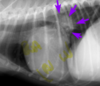

Which statement is true? (R304)

the stomach is empty

the size of the liver is small

there are probably struvite and calcium oxalate stones in the bladder

this is a radiograph of a male cat

there are probably struvite and calcium oxalate stones in the bladder